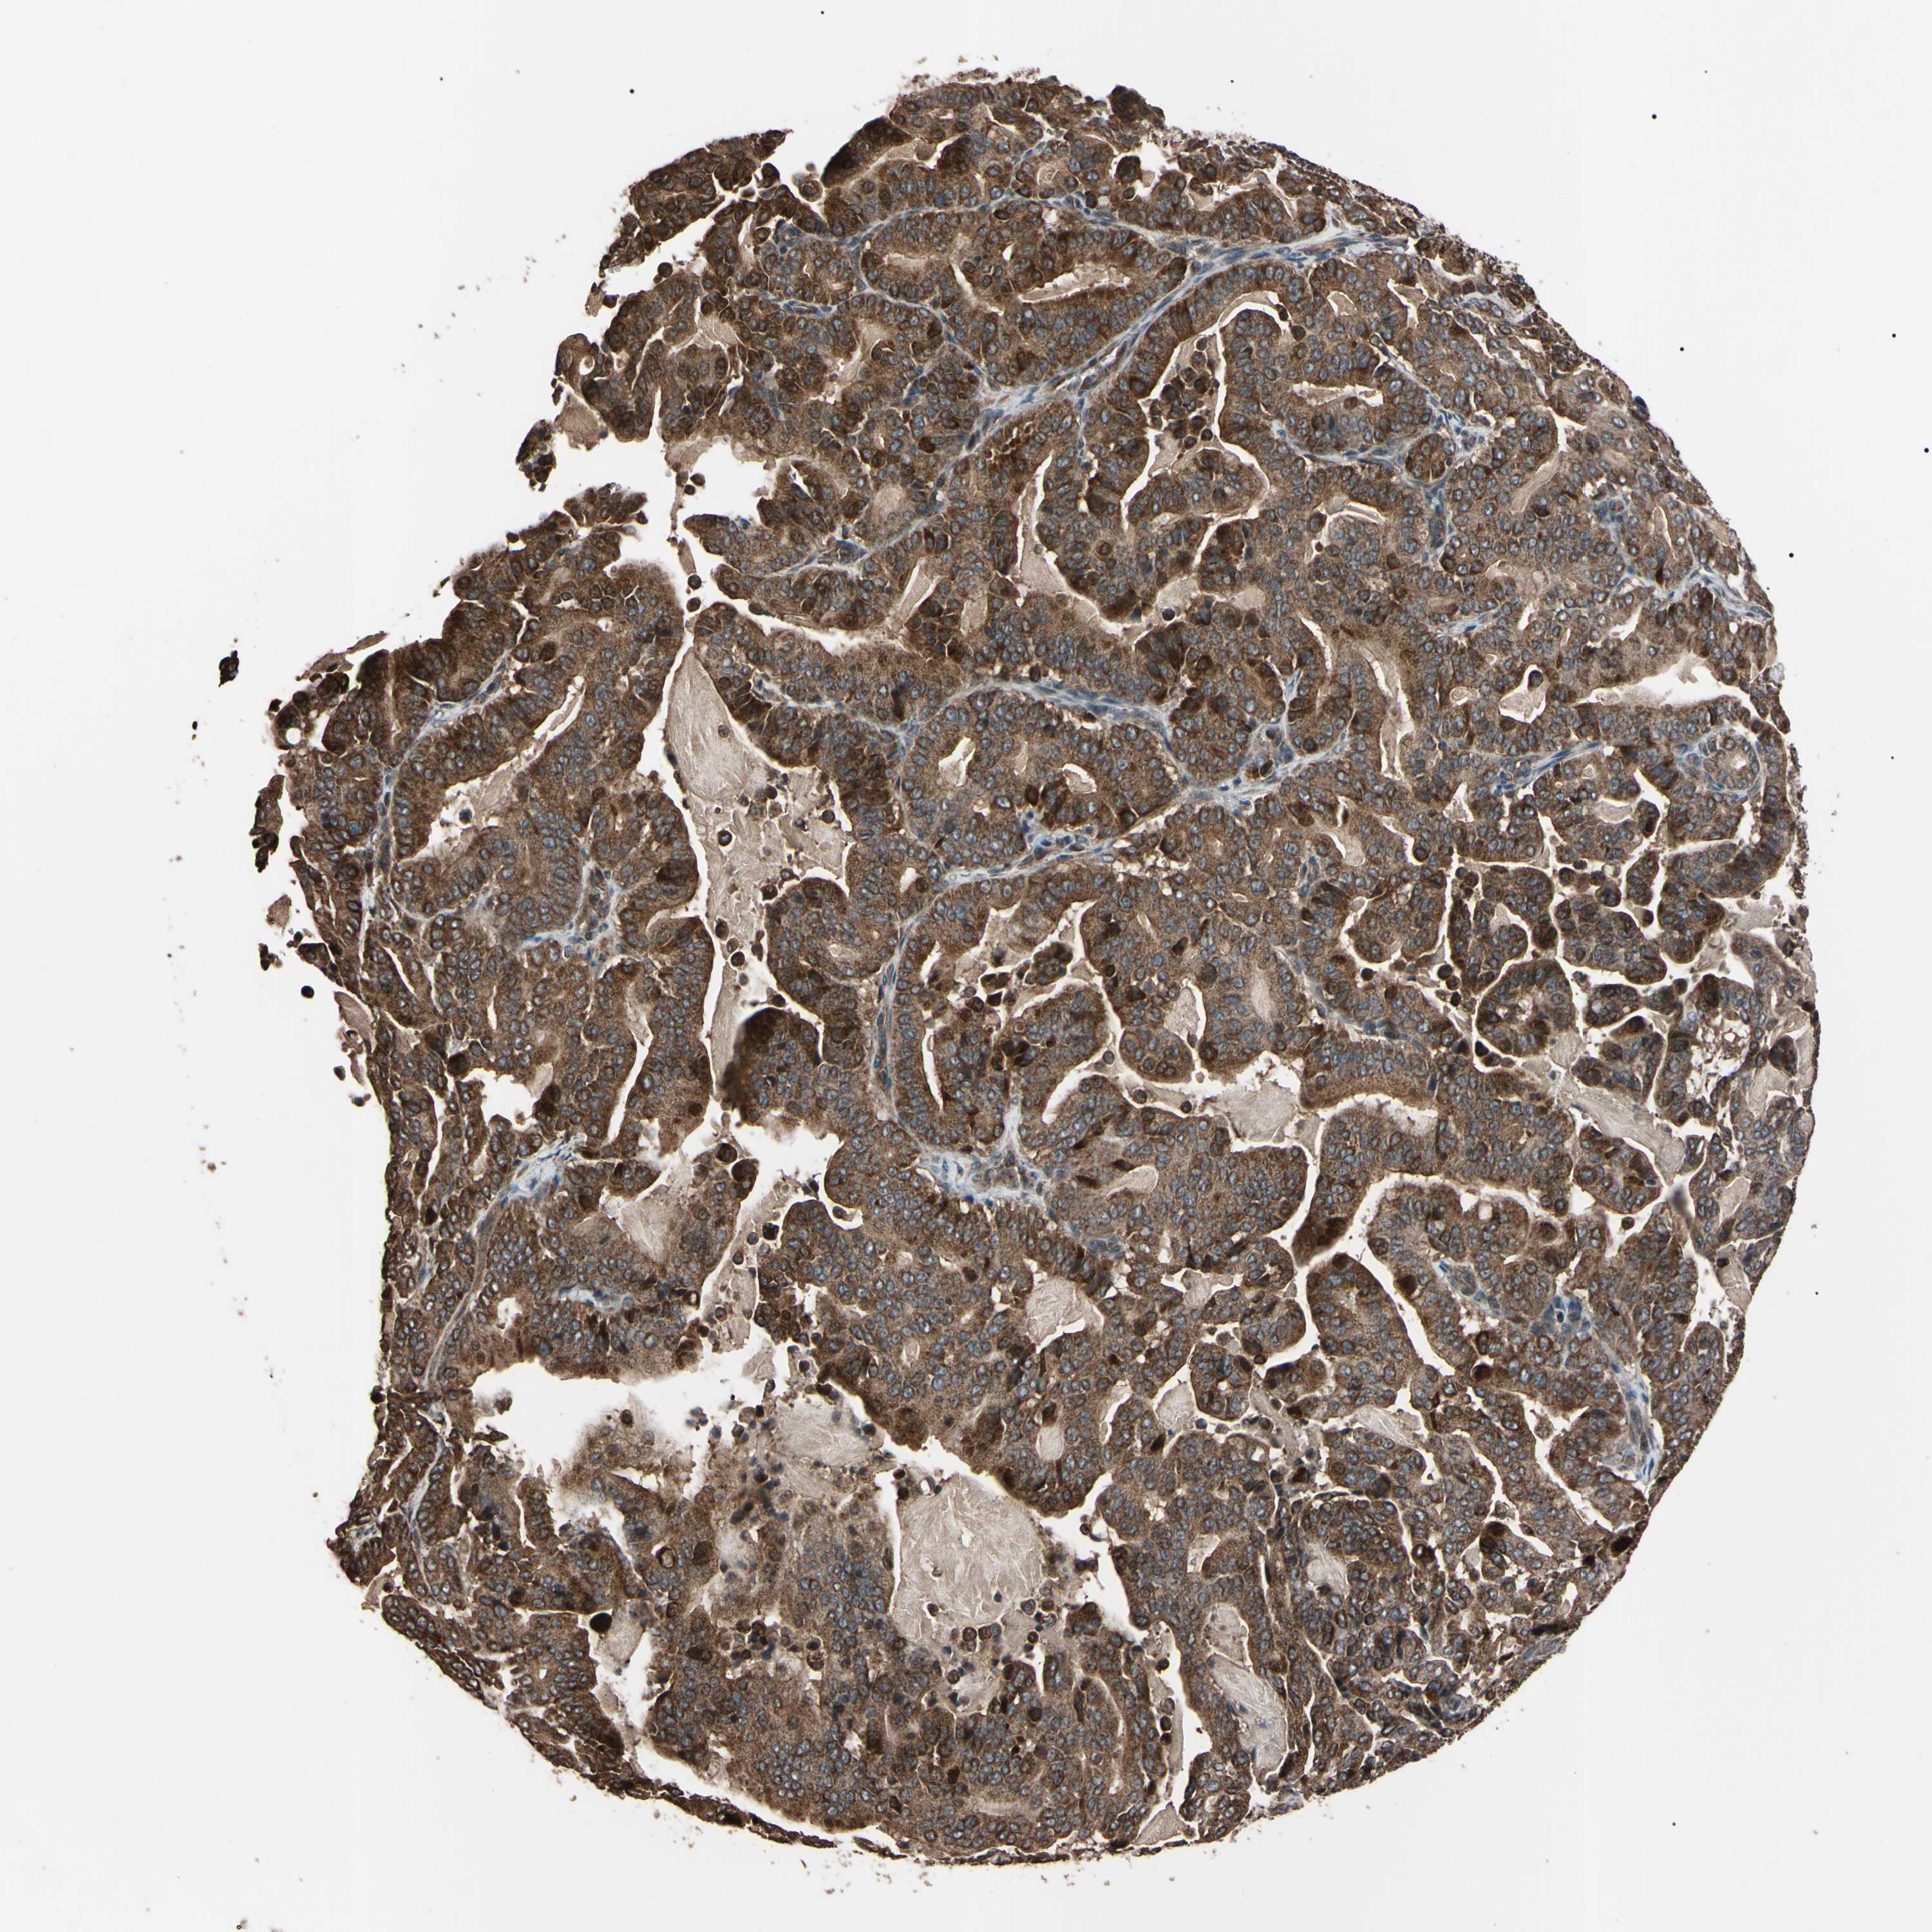

PANCREATIC CANCER - Protein expressioni

A mouse-over function shows sample information and annotation data. Click on an image to view it in a full screen mode. Samples can be filtered based on level of antibody staining by selecting one or several of the following categories: high, medium, low and not detected. The assay and annotation is described here.

Note that samples used for immunohistochemistry by the Human Protein Atlas do not correspond to samples in the TCGA dataset.

Antibody stainingi

Antibody staining in the annotated cell types in the current human tissue is reported as not detected, low, medium, or high, based on conventional immunohistochemistry profiling in selected tissues. This score is based on the combination of the staining intensity and fraction of stained cells.

Each image is clickable and will lead to virtual microscopy that enables deeper exploration of all samples and also displays staining intensity scores, fraction scores and subcellular localization as well as patient and tissue information for each sample.

Antibody HPA004102

Antibody CAB010309

Staining

High

Medium

Low

Not detected

Intensity

Strong

Moderate

Weak

Negative

Quantity

>75%

75%-25%

<25%

None

Location

Nuclear

Cytoplasmic/membranous

Cytoplasmic/membranous,nuclear

Adenocarcinoma, NOS

Adenocarcinoma, metastatic, NOS